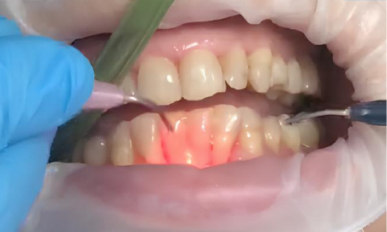

Triplo-1.jpg

1. Подготовка: Пациенту провели профессиональную гигиену полости рта, удалив зубной камень и налёт. Затем выполнили местную анестезию (аппликационную) для обезболивания области лечения.

2. Лазерная обработка: Диодный лазер Medency Primo Triplo был настроен на длину волны 635 нм в режиме «периодонтит», с пародонтологической насадкой 400 мкм. Лазерный луч осторожно направляли на воспаленные ткани пародонтальных карманов для удаления бактериального налёта, стимуляции заживления и уменьшения глубины карманов.